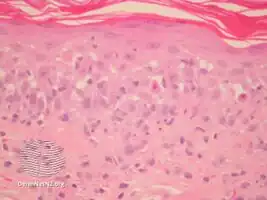

Microscopy of the skin sample obtained from the biopsy is used to detect the presence of cleavage within the dermis, epidermal acantholysis (breaking apart of the skin), dyskeratotic keratinocytes and vacuolar changes in the layers of the skin, interfacial dermatitis, and epidermal exocytosis. Presentation of these characteristics suggests PNP.[1]